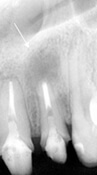

| レントゲン写真上で白っぽくなってきました。 骨が再生されはじめています。 |